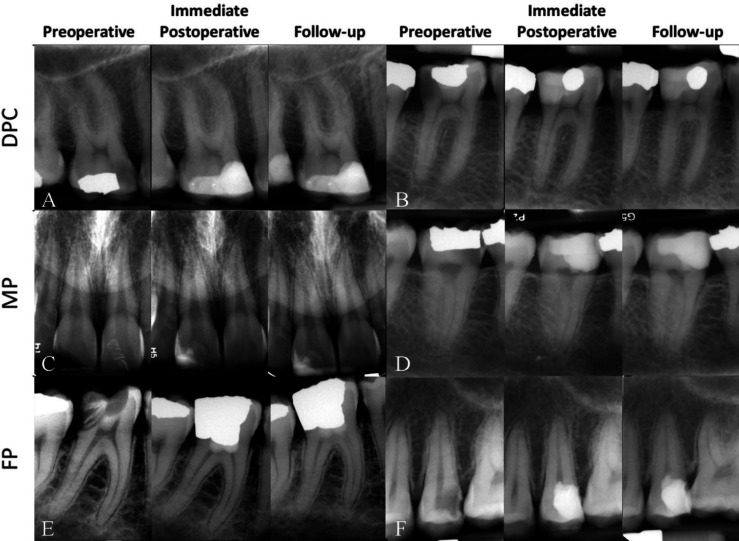

根尖牙周炎(AP)是一种常见的炎症,主要由免疫系统对根管系统内微生物入侵的反应引起。与传统观念相反,根尖周炎可能发生在牙髓发炎的活牙上,从而增加了诊断和治疗的复杂性。由于 AP 常常没有症状,而且需要依靠放射学评估才能发现,因此常常给诊断带来挑战。此外,AP 的发病机制涉及微生物毒力与宿主免疫反应在细胞和分子水平上的复杂相互作用。全面的诊断程序,包括患者病史、临床检查和放射学评估,对于早期发现和必要的干预至关重要,而临床症状和体征的识别则强调了定期牙科评估的重要性。本综述主要讨论了重要牙齿和非重要牙齿 AP 的影像学和临床特征;引入了一种新的分类方法,以提高诊断精度和治疗效果。此外,它还根据牙髓状态以及临床和放射学检查结果,提出了治疗 AP 的不同治疗类别/选择;强调对患有 AP 的重要牙齿和非重要牙齿分别进行重要牙髓治疗和根管治疗。此外,还介绍了 AP 的全球和地区流行病学及其与全身健康状况的关联,如心血管疾病、糖尿病和不良妊娠结局。此外,还提出了未来的研究方向,以提高诊断和治疗的有效性和可预测性,为临床医生早期发现、准确诊断和有效管理 AP 以改善口腔健康状况铺平道路。

Apical periodontitis (AP) is a common inflammatory condition predominantly caused by the response of the immune system to microbial invasion within the root canal system. Contrary to conventional perception, AP may occur in vital teeth with inflamed pulp; adding complexity to diagnosis and treatment. AP, due to its frequent lack of symptoms and reliance on radiographic evaluation for detection, often presents diagnostic challenges. In addition, AP pathogenesis involves complex interactions between microbial virulence and host immune response at the cellular and molecular levels. Comprehensive diagnostic procedures, including patient history, clinical examination, and radiographic evaluation, are essential for early detection and necessary intervention, with the recognition of clinical signs and symptoms underscoring the importance of regular dental evaluations. The current review primarily discusses the radiographic and clinical features of AP in vital and non-vital teeth; introducing a new taxonomic classification to improve diagnostic precision and treatment outcomes. Moreover, it proposes different treatment categories/options for the management of AP, based on pulp status as well as clinical and radiographic findings; emphasizing vital pulp therapy and root canal treatment for vital and non-vital teeth with AP, respectively. Furthermore, the global and regional epidemiology of AP is presented, along with its association with systemic health conditions; e.g., cardiovascular diseases, diabetes mellitus, and adverse pregnancy outcomes. Moreover, future research directions are advocated to improve the efficacy and predictability of diagnosis and treatments; paving the path for clinicians in early detection, accurate diagnosis, and effective management of AP to enhance oral health outcomes.